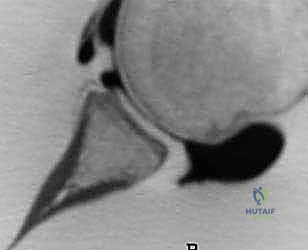

عندما يتآكل العظم في الجزء الأمامي السفلي من التجويف الحقاني بسبب الخلوع المتكررة، يتحول شكل التجويف من شكل "الكمثرى" الطبيعي إلى شكل "التفاحة المقطوعة" أو "الكمثرى المقلوبة". هذا الفقدان يقلل من مساحة السطح التي تستقر عليها الكرة، مما يجعل من السهل جداً انزلاقها خارج المفصل حتى مع الحركات البسيطة مثل ارتداء الملابس، أو الوصول إلى شيء في الخلف، أو أثناء النوم.

- الأشعة المقطعية ثلاثية الأبعاد (3D CT Scan): وهي الخطوة الأهم. تتيح هذه الأشعة للدكتور هطيف حساب النسبة المئوية الدقيقة لفقدان العظم في التجويف الحقاني (Glenoid Bone Loss) وتحديد حجم عيب "هيل-ساكس" (Hill-Sachs lesion) في رأس عظم العضد. إذا تجاوز الفقدان العظمي 15-20%، تكون عملية لاتارجيه هي الخيار الأوحد والأمثل.